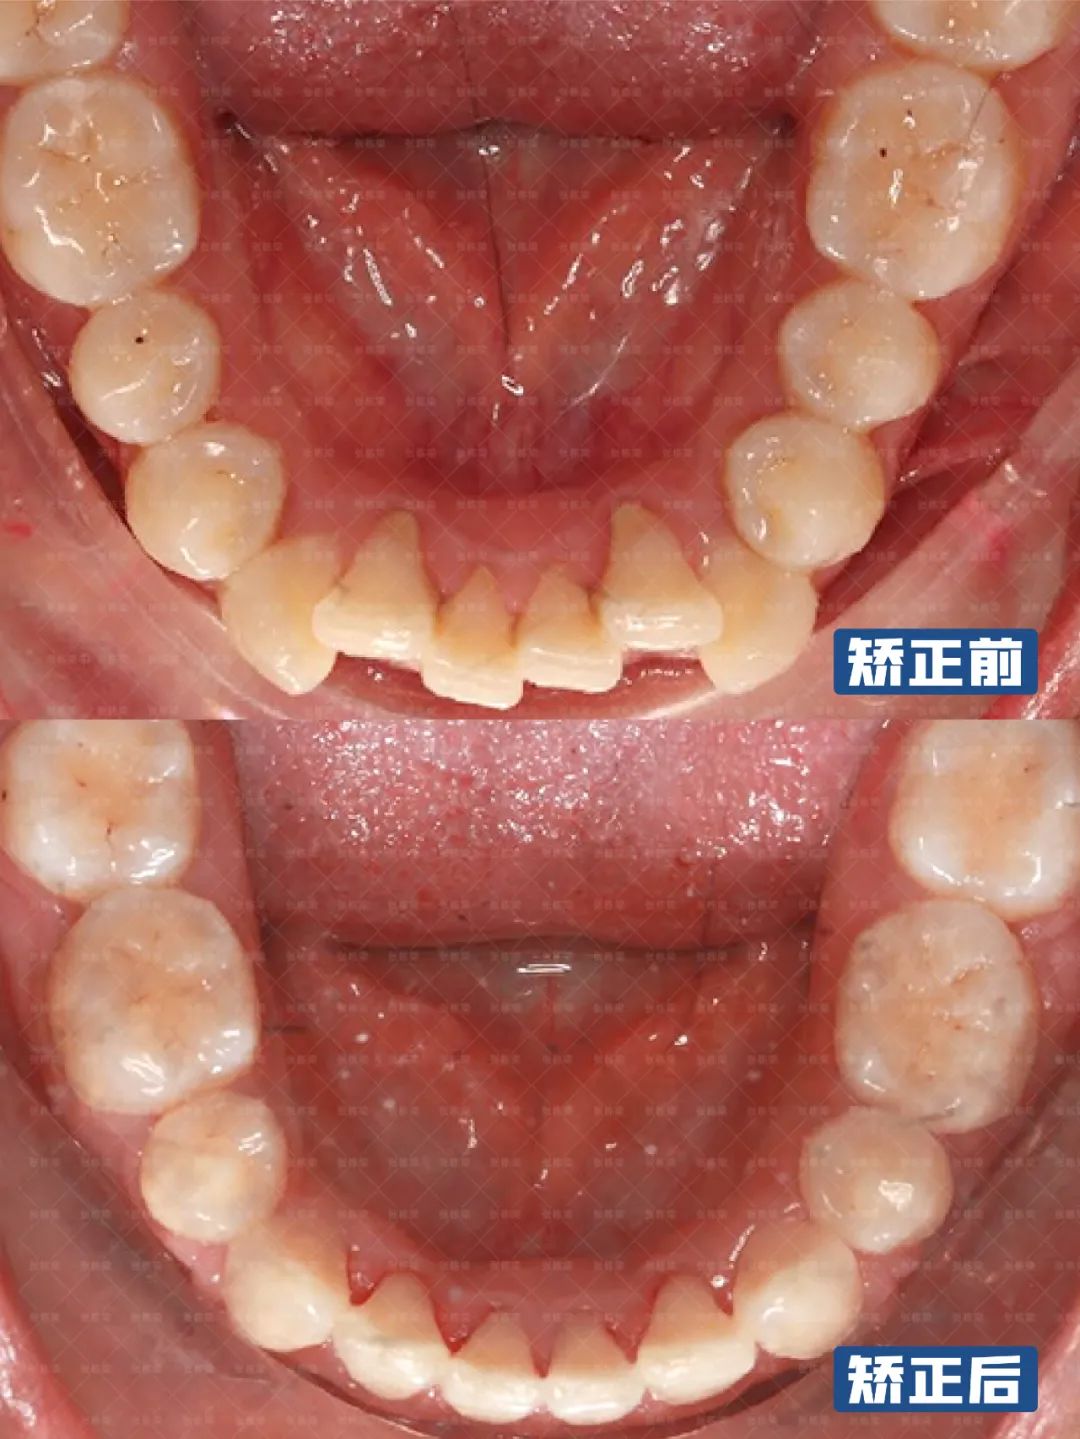

1、正面观:面部双侧右侧偏大,左侧偏小,颏点正中,面下1/3高度正常,无露龈笑,闭嘴时颏肌紧张,开唇露齿,上中线正;6、牙列:恒牙列,上下前牙唇倾,上牙弓尖圆形,ll度拥挤,下牙弓方圆形,lll度拥挤;

女士了解到自己的详细情况,想要比较大的改善,因此制定拔除正畸牙的矫正方案,上下颌拔除14,24,34,44,关闭间隙,同时建立后牙高度,稳定咬合。

另外在牙齿矫治过程中及时调整尖牙的转矩角度,整平颌平面倾斜角度,引导下巴前伸。从健康角度来看,牙齿和咬合都恢复良好,从面型美观来看,前凸问题得到很大的改善,上下嘴唇收到审美E线以内,颏部明显,面下三分之一协调感刚刚好,脸型也随之发生了变化,唇部形态也好看了。